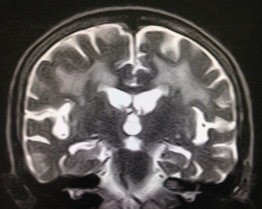

虚血性心疾患の既往もあり。認知機能テストは低得点。MRIも裏付ける内容。他スライスでも明らかな、広汎な白質病変を伴う左右差のある強烈な海馬萎縮。AGDを疑わせるような行動異常は認めず。アルツハイマーにおける海馬萎縮の左右差頻度は拙著に記載した通り、珍しくもなし。年齢的にNFTDとの鑑別は当然だが、過剰リン酸化タウオンリーよりも、アミロイドβ+過剰リン酸化タウのコラボがこの強烈な海馬萎縮の元凶と“妄想”。処方されていたメマリーでノイズを消すことよりも、既往歴と白質病変から考えるに優先すべきことがあるのでは❓

90代前半の症例。風貌は“長身の老紳士”。記憶の問題あり。虚血性心疾患の既往もあり。認知機能テストは低得点。MRIも裏付ける内容。他スライスでも明らかな、広汎な白質病変を伴う左右差のある強烈な海馬萎縮。AGDを疑わせるような行動異常は認めず。アルツハイマーにおける海馬萎縮の左右差頻度は拙著に記載した通り、珍しくもなし。年齢的にNFTDとの鑑別は当然だが、過剰リン酸化タウオンリーよりも、アミロイドβ+過剰リン酸化タウのコラボがこの強烈な海馬萎縮の元凶と“妄想”。処方されていたメマリーでノイズを消すことよりも、既往歴と白質病変から考えるに優先すべきことがあるのでは❓